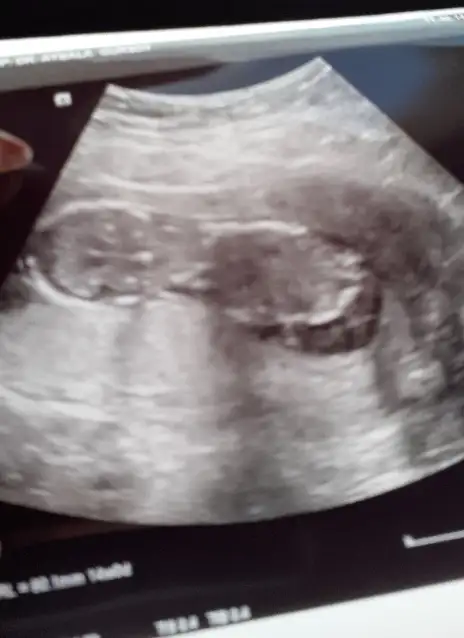

Kızlar bende şimdi çıktım herşey yolunda çok şükür ense kalınlığıda iyi ikili test biz istemedik cinsiyet kıza benziyor dedi ama en iyi bı ay sonra beli olur geçen hafta da devlet hastanesindeki doktor erkeğe benziyor demişti kafam iyice karıştı hayırlısı olsun inşallah çok güzel oynuyordu 12+2 haftalık miş